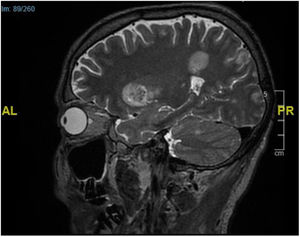

Pruebas complementariasSe realizaron 2 biopsias cutáneas en una placa y un nódulo subcutáneo. El examen histopatológico confirmó una presencia considerable de hifas alargadas y septadas invadiendo la dermis y la epidermis hasta el estrato córneo (fig. 2A). También se observó una extensa necrosis adiposa similar a la paniculitis e hifas en el interior del tejido adiposo (fig. 2B). Antes de la confirmación micológica, el paciente quedó en estado de obnubilación. La TC cerebral de urgencia reveló la presencia de lesiones parenquimatosas compatibles con émbolos sépticos. La resonancia magnética posterior (fig. 3) confirmó estos hallazgos.

DiagnósticoAspergilosis cutánea diseminada.